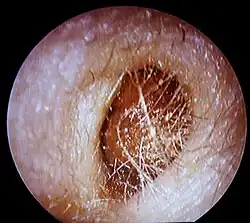

Bouchon de cérumen complet dans le conduit auditif